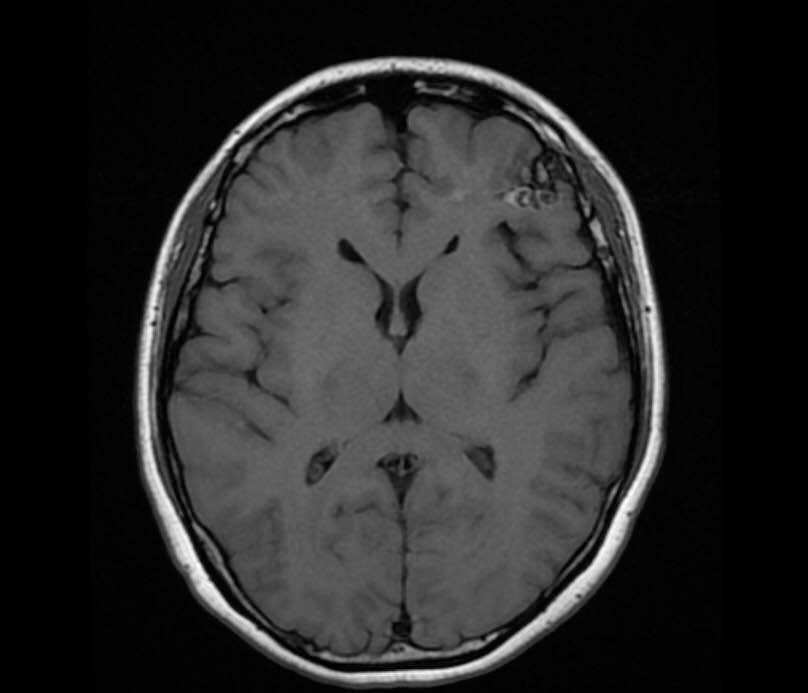

病人….被另一名曾經嚴重腦出血性中風(腦動脈瘤破裂以致嚴重的蜘蛛綱膜下腔出血及曾經瞳孔放大和深度昏迷…其後完全康復)的病人介紹…..帶MRI 底片到我診所尋求第二醫療諮詢….. 其時心情亦愉快…….直到….看了MRI 影像後…..我告訴她真正的MRI檢查結果……她的左前腦額葉上….有一個3cm大的腦動靜脈畸形血管瘤(AVM).. ….亦有最近出過血的跡象…可能是她失去意識和腦癇症的原因。

兩天後….在私家醫院為她做診斷式的動態腦血管造影來確定䐉血液的流動模式後,再進行了4 小時的顯微鏡手術….AVM的計時炸彈完全切除……..在AVM旁邊的腦部亦能看到血鐵黃素的舊有殘留血液。手術後兩天出院。